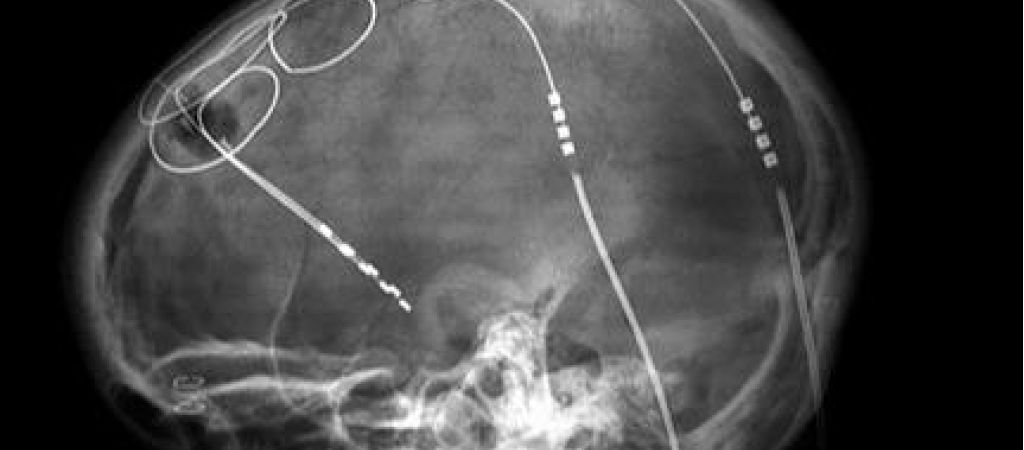

Eind jaren 90 pasten neurochirurg prof. dr. Bart Nuttin en zijn team van UZ Leuven als eersten ter wereld diepe hersenstimulatie toe bij vier patiënten met een dwangstoornis. In 2016 volgde een dubbelblinde, gecontroleerde klinische studie die de veiligheid en werkzaamheid aantoonde bij 24 Leuvense patiënten. Recent publiceerde het team een nieuwe studie waarin 30 patiënten met diepe hersenstimulatie langdurig werden opgevolgd.

In plaats van een klassiek klinisch onderzoek, kozen ze voor een real-worldstudie zonder controlegroep en zonder strikte selectie van de testpersonen, waarbij meerdere Europese centra betrokken waren. Neurochirurgen van over heel Europa kwamen in Leuven langs om de techniek te leren of het team werd bij hen uitgenodigd om ze te tonen. Dat is een belangrijke meerwaarde van deze real-worldstudie, want een behandeling is pas echt succesvol als ze wereldwijd in de handen van meerdere neurochirurgen en psychiaters werkt.

Hersenstimulatie leidde bij de meeste patiënten tot een sterke vermindering van de symptomen. Uit de verschillende studies blijkt ook dat het positieve effect langdurig aanhoudt: patiënten waarbij de ingreep vanaf het begin goede resultaten had, bleken hun dwangstoornis dankzij hersenstimulatie 15 jaar later nog altijd onder controle te hebben”, vertelt professor Nuttin op de site van UZ Leuven.